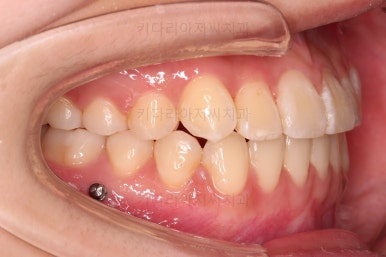

덧니가 완전히 개선디ㅗ었고 필요한 충치치료도 부분적으로 진행했고요.

중앙선이나 교합도 양호하게 마무리 했습니다.

환자분이 원하는 포인트들이 다 개선되었고요.

웃을 때 보이는 느낌도 많이 좋아졌네요.

옆라인도 입이 안나오게 비발치 교정 마무리 잘 되었고요.

묘하게 옆라인의 곡선이 더 예뻐졌죠?

충치도 틀린그림 찾기 수준으로 진짜 필요한 몇 개만 치료를 하고 연산동교정치과 마무리를 했습니다. 어차피 유지관리 체크를 꾸준히 내원하실 거기 때문에 지켜보기로 했습니다.

이상 미니스크류를 이용해 비발치로 덧니 치아를 교정치료한 사례였습니다.